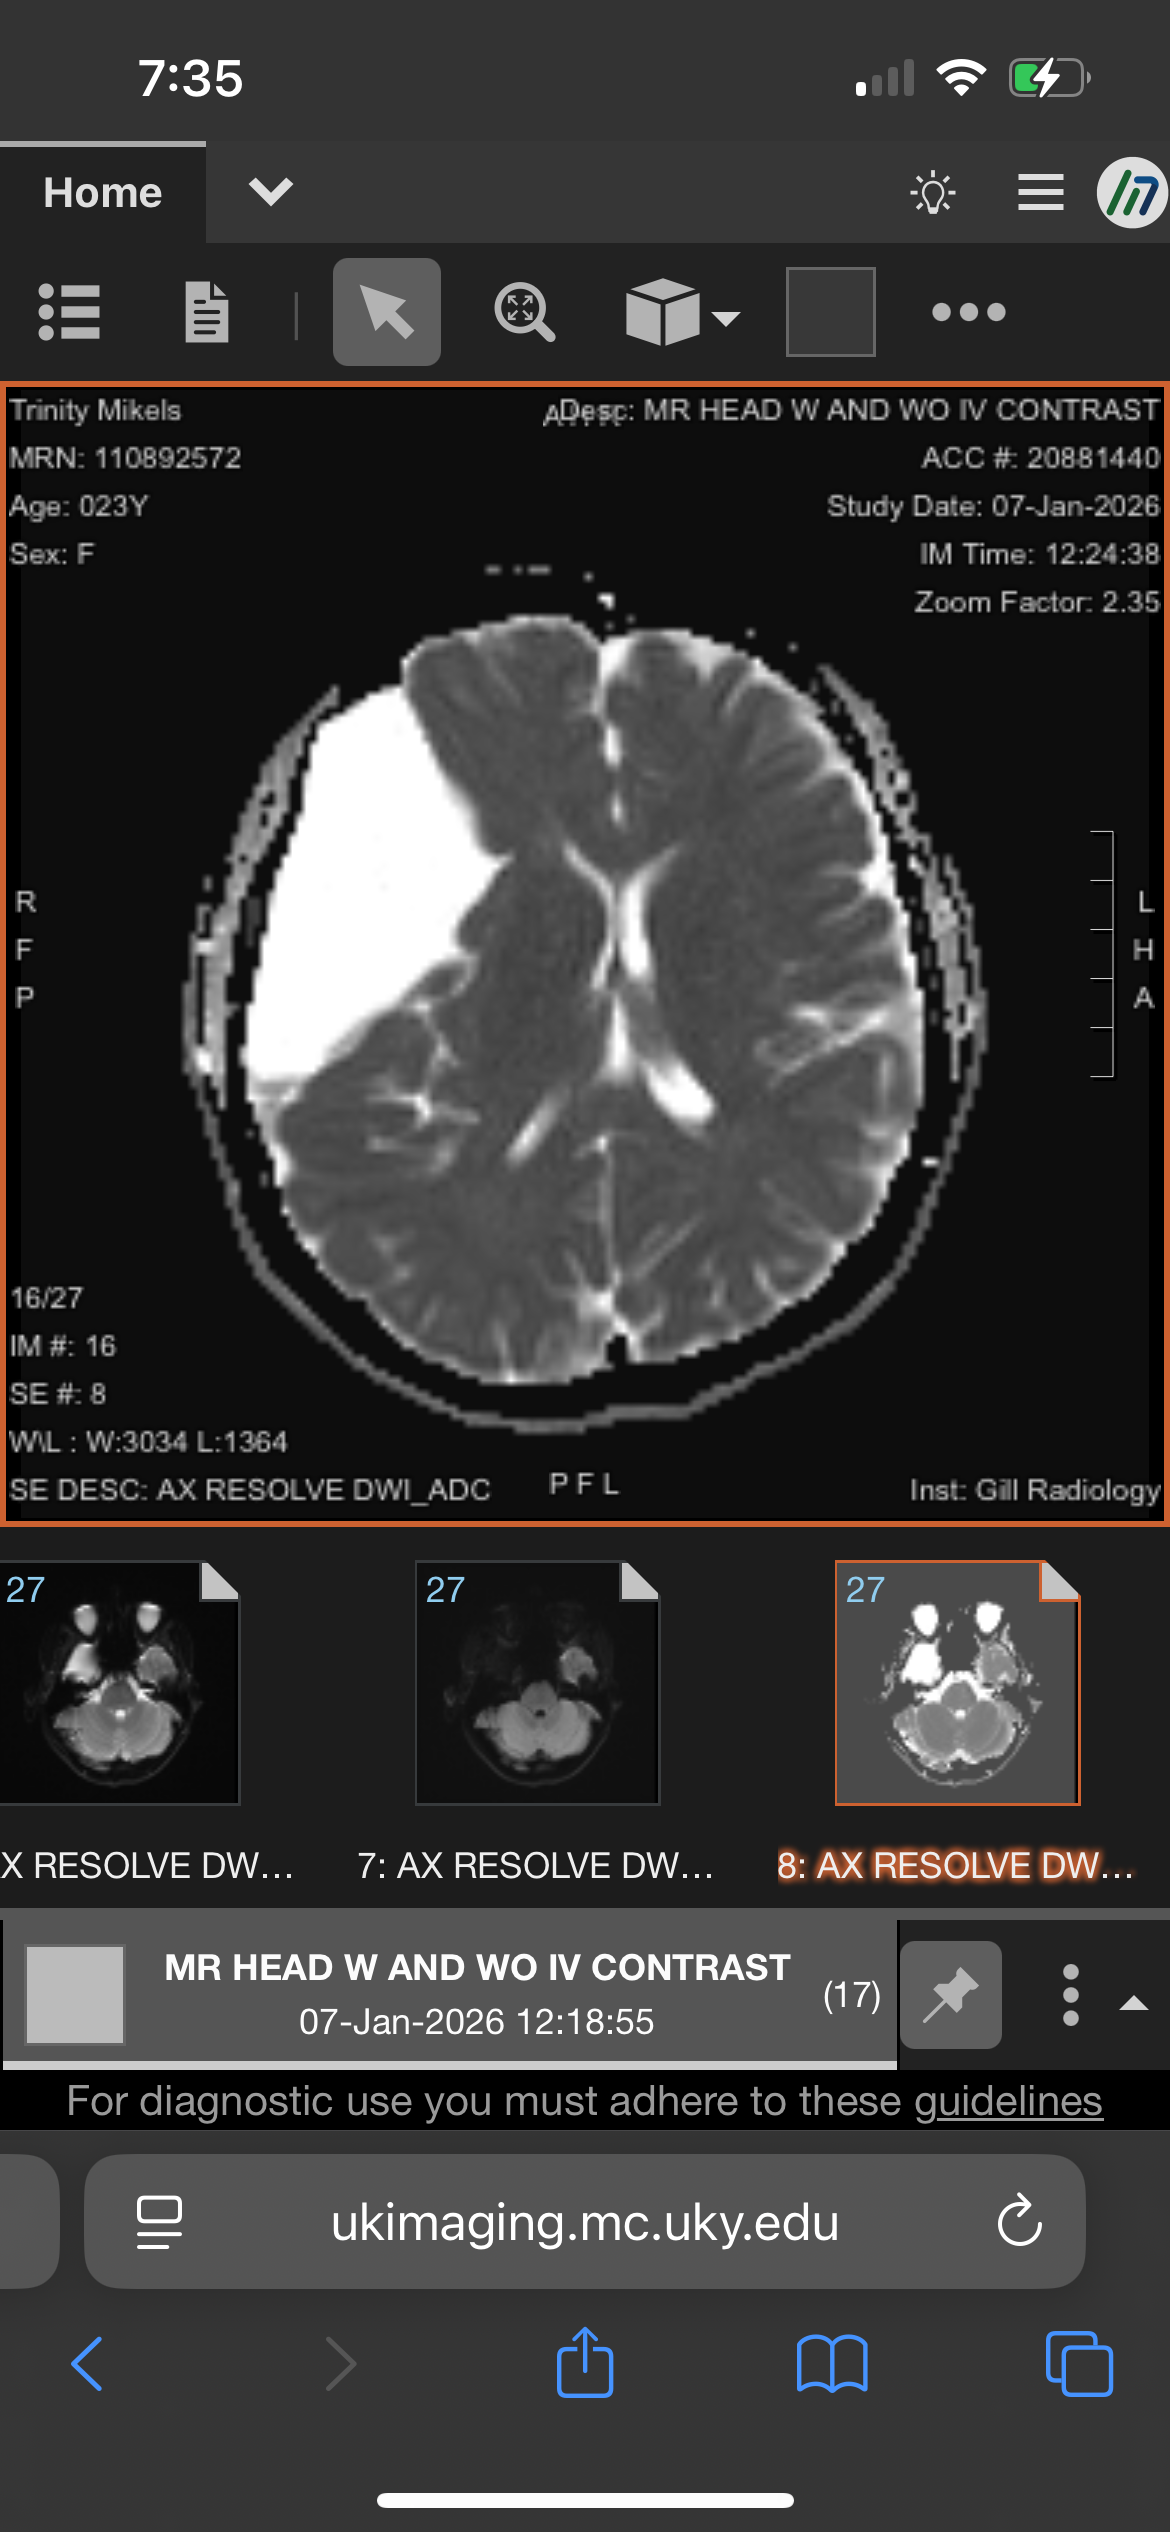

On January 7, at UK Hospital in Lexington, an in-depth MRI confirmed that Trinity has a very large (and rare) arachnoid cyst on the right side of her brain. While arachnoid cysts themselves are not uncommon, the size of Trinity’s cyst is rare. The cyst is pressing against the inside of her skull, located in front of her right eye, and has shifted her entire brain toward the left side of her head. (Images of her CT and MRI scans have been shared; please be advised if you choose to view them.)

On January 7, at UK Hospital in Lexington, an in-depth MRI confirmed that Trinity has a very large (and rare) arachnoid cyst on the right side of her brain. While arachnoid cysts themselves are not uncommon, the size of Trinity’s cyst is rare. The cyst is pressing against the inside of her skull, located in front of her right eye, and has shifted her entire brain toward the left side of her head. (Images of her CT and MRI scans have been shared; please be advised if you choose to view them.)